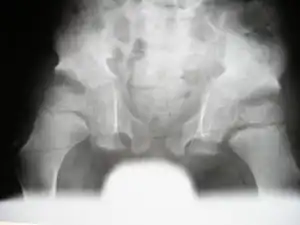

( Marshall-Stickler overlap) Anteroposterior pelvis radiograph showed, coxa valga, a hypoplastic ileae, acetabulo-femoral and metaphyseal dysplasia